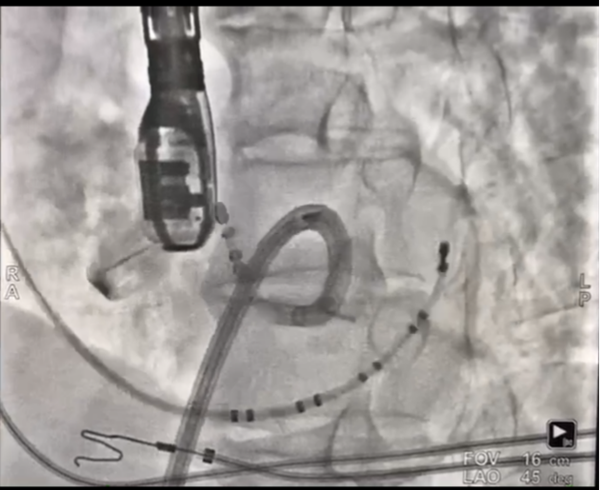

患者进入手术室麻醉后,室早消失,薛荣亮主任和李伟主任对麻醉药物精确滴定,既保证有稳定的室早出现,又保证患者的麻醉效果。超声室金鑫医师迅速实施食道超声插管。心内科郑强荪主任、王洪涛医师、郝广华医师和苏丹医师随即实施手术。首先穿刺股动脉,将消融导管逆行送入主动脉窦部位,在主动脉金属瓣上谨慎操作,行激动标测,未标记到室早最早激动点。考虑患者存在主动脉瓣金属瓣,消融导管不宜直接跨瓣膜操作,遂穿刺股静脉,在食道超声指导下行房间隔穿刺,将可调弯鞘管和消融导管依次送入左房、左室,以非同平面双弯角度最终把消融电极成功送入主动脉瓣下,标记到室早最早激动点。随着放电消融的“滴滴声”,10秒后,室早即刻终止。逐步增加功率,巩固消融后,室早未再出现,大家如释重负。术后持续心电监护显示,室早一个都没有出现,彻底解决了困扰患者多年的心悸问题。

主动脉瓣下激动标测和射频消融